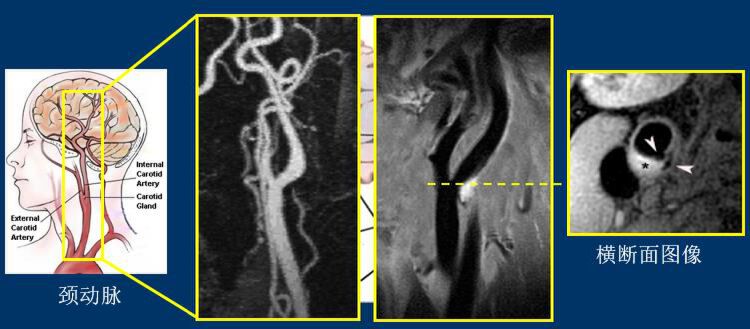

(左边是现有技术下的血管造影结果,白色为血管。右边是血管壁成像技术拍出的结果,黑色的为血管。)

“通过血管造影结果看这位病人的血管是没有什么问题的,但在血管壁成像下可以看到,颈动脉分岔的地方有一个斑块,白色高亮部分。调取横断面图像可以看到,病人斑块旁有一个缺口,脱落的斑块从缺口跑出来,形成血栓,堵塞血管。”